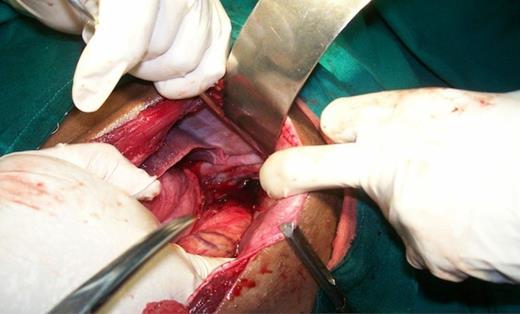

The patient was counseled and prepared for surgery through a left sub costal incision. The findings at surgery were that two-thirds of the stomach, omentum and spleen had herniated through a 10cm X 7cm tear in left hemidiaphragm into the chest. (Figure 3) Contents were normal and reduced into the abdomen. An intercostal chest tube drain was guided in the left thoracic cavity. Diaphragmatic tear was repaired with horizontal mattress prolene suture. Postoperative period was uneventful. Follow-up after 1 year showed no recurrence.